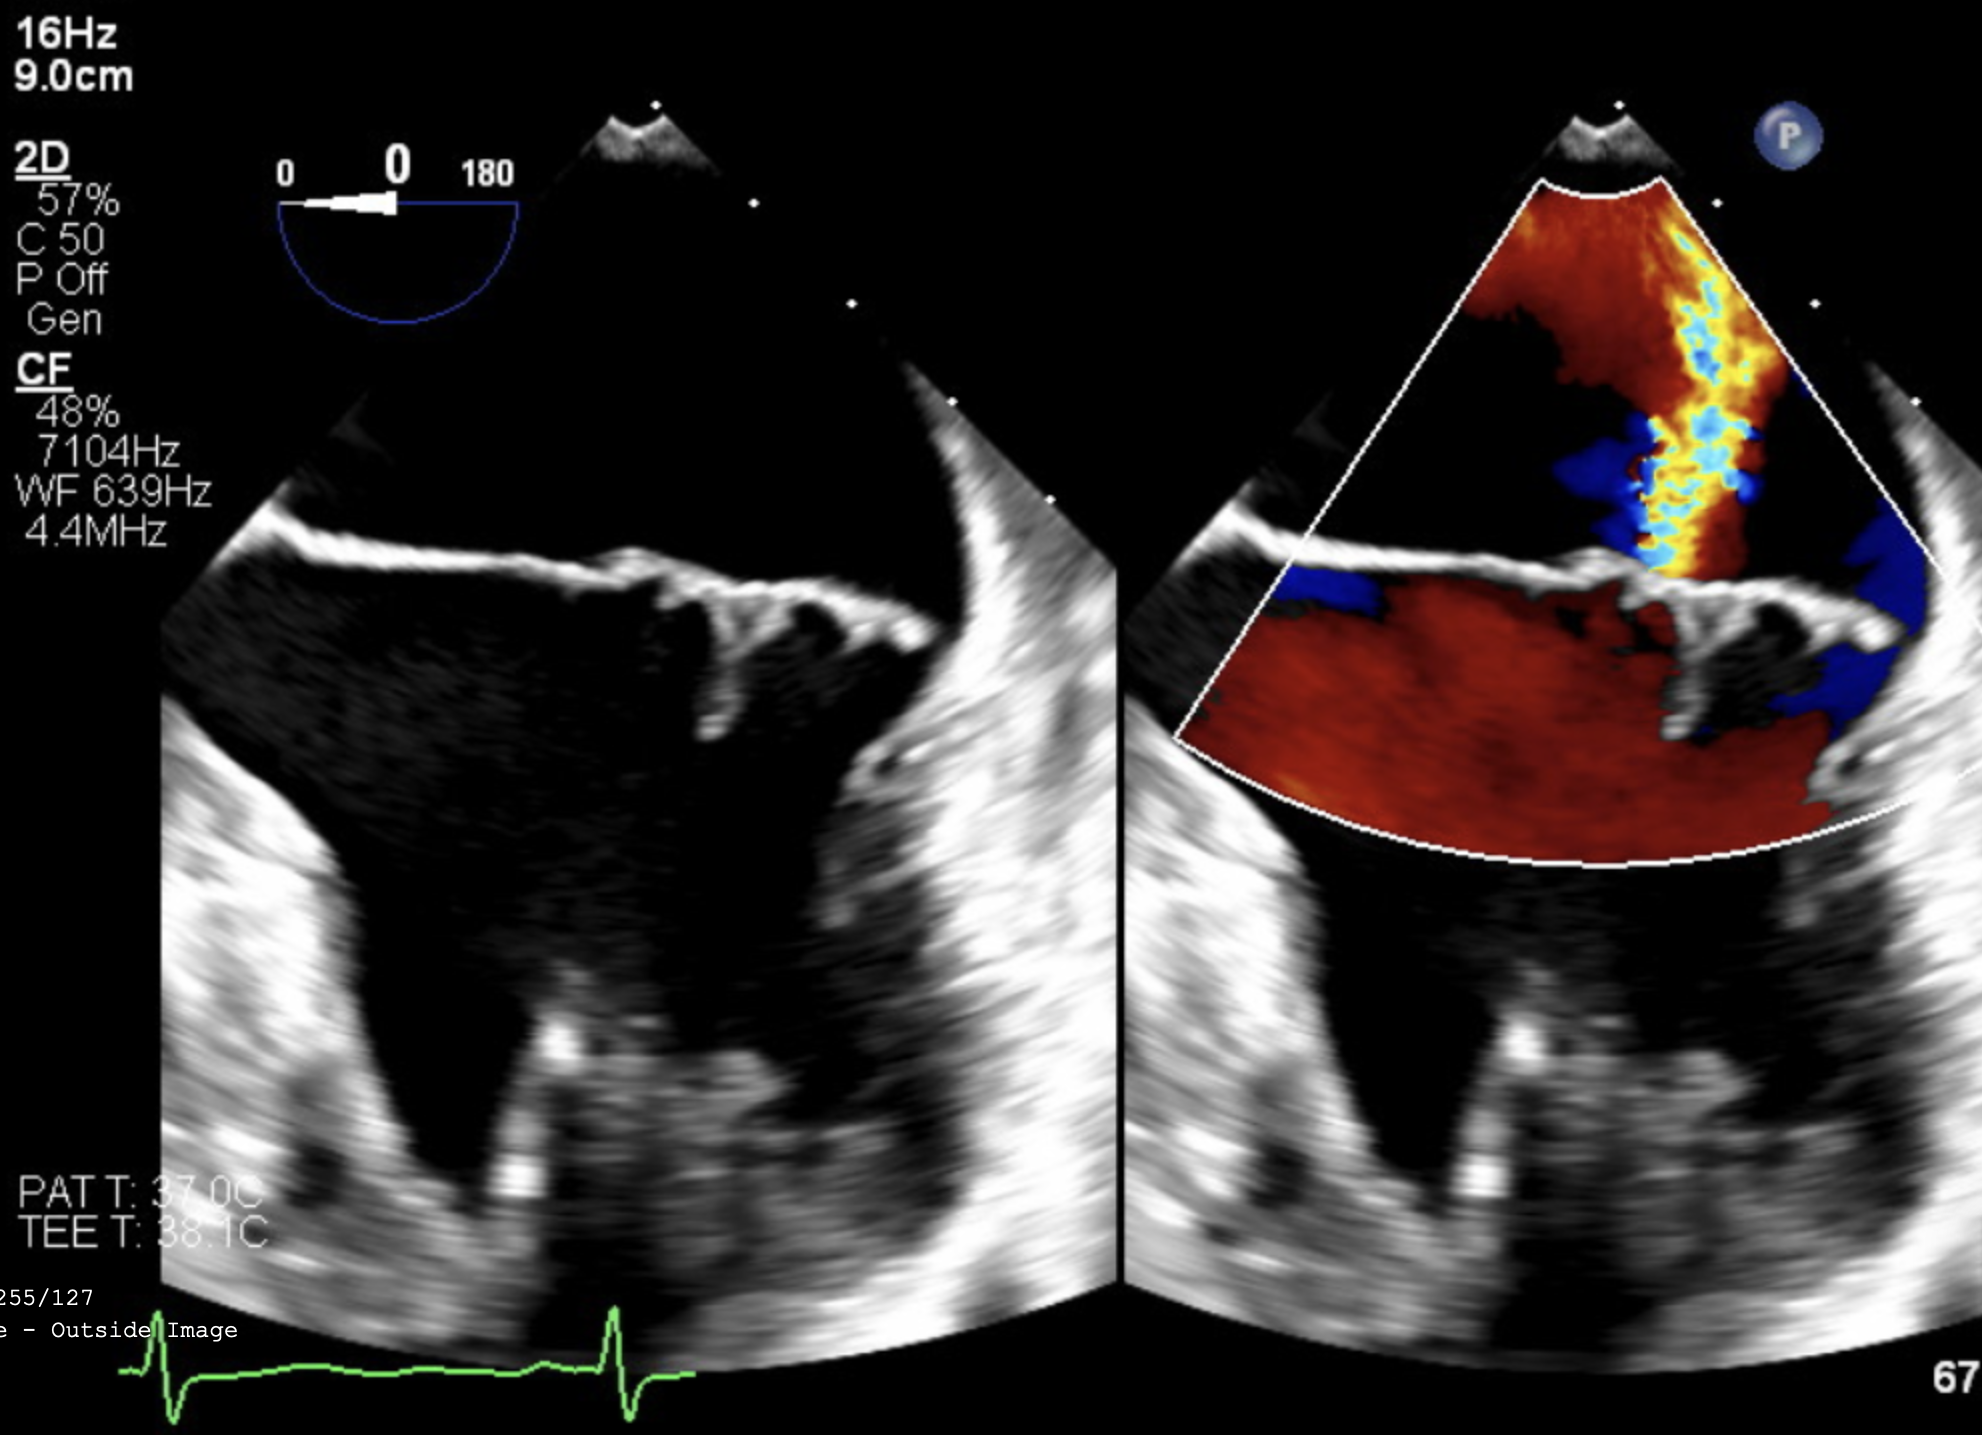

Direct Image Integration

Native imaging at your fingertips

View raw DICOM and other imaging files directly in VerixAi—no external software needed. Imaging data syncs with clinical records for seamless, context-rich expert review.

• VerixAi™ includes embedded imaging viewers, enabling you to review radiology and other large files directly alongside the medical record—without needing to switch between multiple systems.